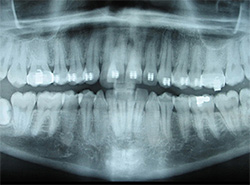

x-rayUsing the most advanced dental technology possible is just as important as staying up-to-date on the latest treatment techniques. Because our practice is dedicated to providing you with the safest and most convenient treatment options available, we utilize advanced digital X-ray technology in our office.

Digital X-rays provide several advanced imaging options, designed to save time, provide clearer dental photos, and expose patients to less radiation than with traditional X-ray technology.

Our practice is focused on making your dental experience as comfortable as possible. At your next appointment, we’ll be happy to answer any questions you may have.